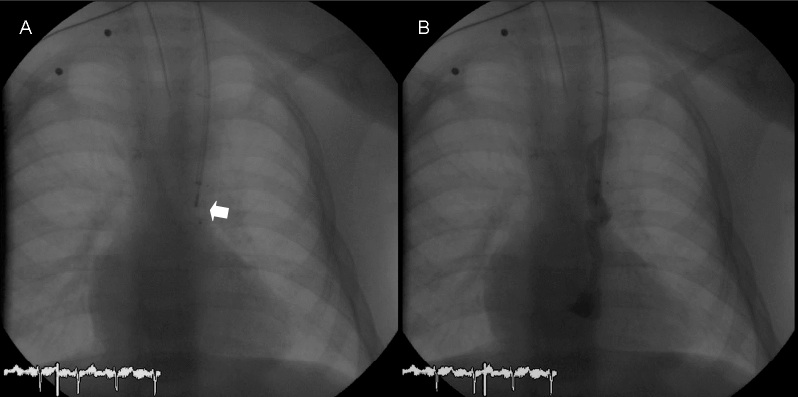

Under general anaesthesia, right heart catheterization was performed using a left internal jugular vein approach. Heparin was administered following our institutional protocol (100 IU per kilogram). A 6 French (Fr) sheath was inserted and a 5 Fr Berman catheter was used for hemodynamic assessment. Angiography showed a tortuous vessel (maximum diameter 6 mm) arising from the innominate vein and draining into the right atrium, corresponding with a left-sided superior vena cava (SVC) with high probability (Figure 1). A multipurpose catheter (MP1 4 Fr) was used to selectively cannulate the vessel and a 0.035 inch exchange wire was then positioned far into it. Over the wire, a 5 Fr guiding catheter was placed and an 8 mm Amplatzer vascular occluder (AGA Medical Corp., Plymouth, Minnesota) was deployed into the narrowest point of the vein (Figure 2A). Before releasing it, control angiography (Figure 2B) showed a significant residual shunt, and it was decided to use a larger device. A new 6 Fr guiding catheter was positioned into the vessel, and a 10 mm device was placed. An angiography performed 5 minutes later showed significant residual patency of blood flow. Thus, a 5 Fr Berman angiography catheter was positioned proximal to the plug and inflated for 10 minutes in order to interrupt the flow in the collateral vein (Figures 3A and 4). A new angiogram confirmed the absence of blood flow (Figure 3B). Subsequent control angiograms excluded the presence of other relevant collateral vessels. A significant rise in arterial blood saturation was noted (from 83% to 97%) immediately after the procedure.